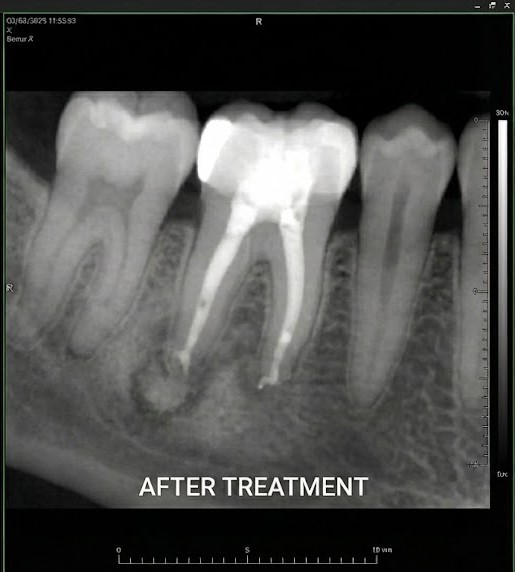

Our endodontic dentists use rotary instruments, digital imaging and microscope-assisted techniques to deliver precise, comfortable care. We also provide retreatment and apicoectomy for complex cases where a previous root canal has failed. By preserving your natural tooth whenever possible, endodontic care often provides a more stable long-term solution than extraction and replacement. Endodontic care includes root canal therapy to treat active infection and retreatment when a previous root canal needs further care to preserve the tooth.

Our endodontic specialists use advanced microscopes and digital imaging to perform precise treatment. Unlike general dentistry, microscopic endodontics helps identify hidden canals and address complex infections while preserving as much natural tooth structure as possible.

Yes. Microscopic endodontics allows our specialists to treat complex canals with greater accuracy. Magnification helps improve outcomes, especially in retreatment or complicated cases.

Under local anaesthetic, your endodontist makes a small opening in the tooth, removes the infected pulp and cleans and shapes the canals. They then fill the canals with a biocompatible material and seal the tooth. A crown is placed later to restore function.

If a previously treated tooth doesn’t heal properly or becomes reinfected, retreatment can reopen the tooth, remove the old filling material, disinfect the canals and reseal them. This gives the tooth another chance for success.